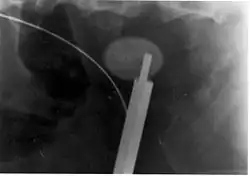

Where a CT scan is unavailable, an intravenous pyelogram may be performed to help confirm the diagnosis of urolithiasis. This involves intravenous injection of a contrast agent followed by a KUB film. Uroliths present in the kidneys, ureters, or bladder may be better defined by the use of this contrast agent. Stones can also be detected by a retrograde pyelogram, where a similar contrast agent is injected directly into the distal ostium of the ureter (where the ureter terminates as it enters the bladder).[61]

Renal ultrasonography can sometimes be useful, because it gives details about the presence of hydronephrosis, suggesting that the stone is blocking the outflow of urine.[59] Radiolucent stones, which do not appear on KUB, may show up on ultrasound imaging studies. Other advantages of renal ultrasonography include its low cost and absence of radiation exposure. Ultrasound imaging is useful for detecting stones in situations where X-rays or CT scans are discouraged, such as in children or pregnant women.[67] Despite these advantages, renal ultrasonography in 2009 was not considered a substitute for noncontrast helical CT scan in the initial diagnostic evaluation of urolithiasis.[66] The main reason for this is that, compared with CT, renal ultrasonography more often fails to detect small stones (especially ureteral stones) and other serious disorders that could be causing the symptoms.[14]